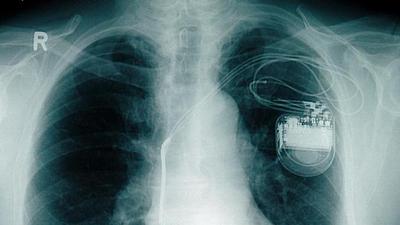

Marca-passo sem bateria é testado com sucesso em porcos

Dispositivo obtém energia a partir dos próprios batimentos cardíacos. Caso funcione em seres humanos, invenção pode representar um grande alívio para pacientes com o implante.